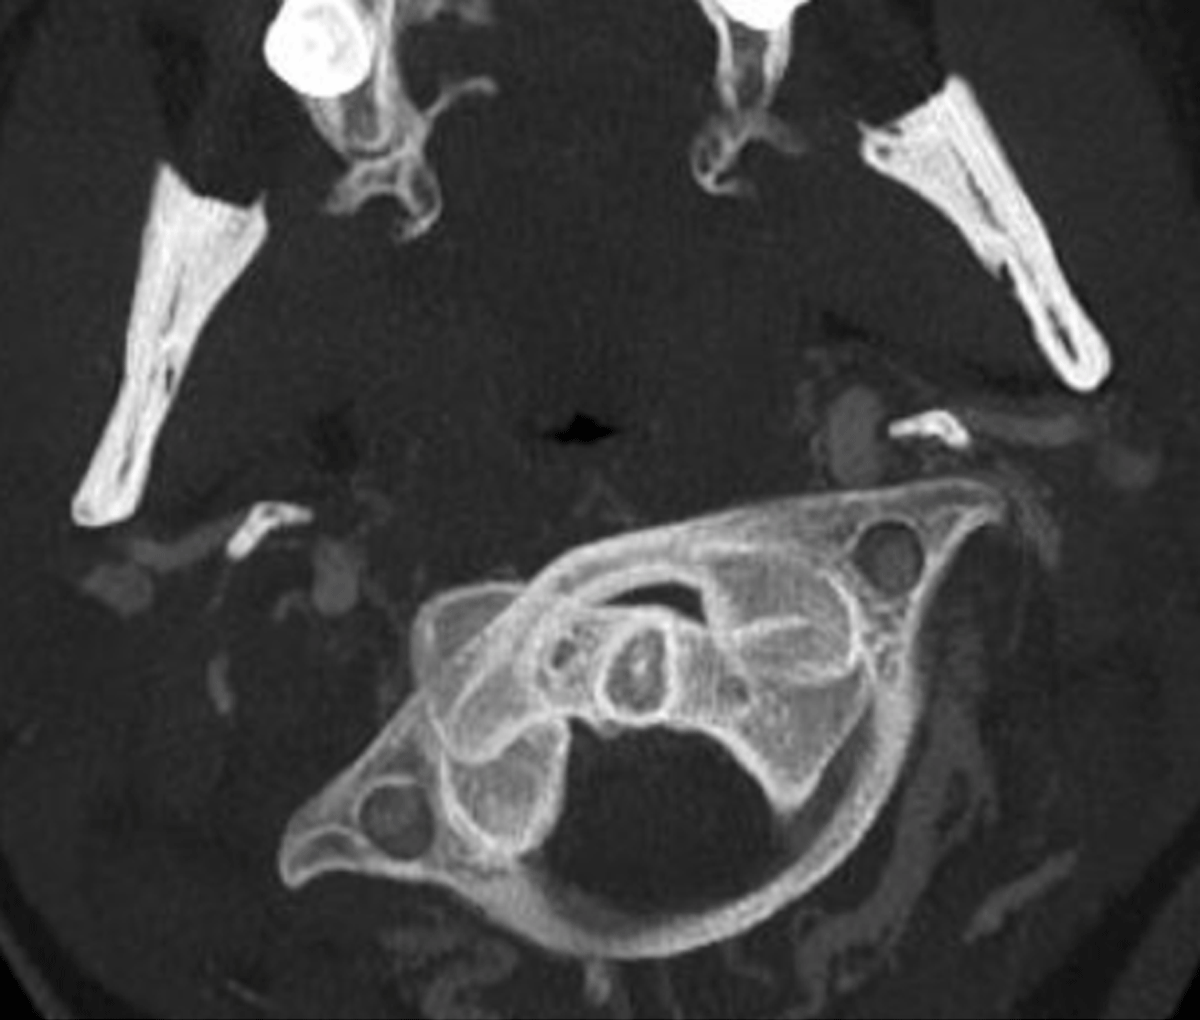

Figure 1

Rotation of C1 on C2 on CT in neutral position.